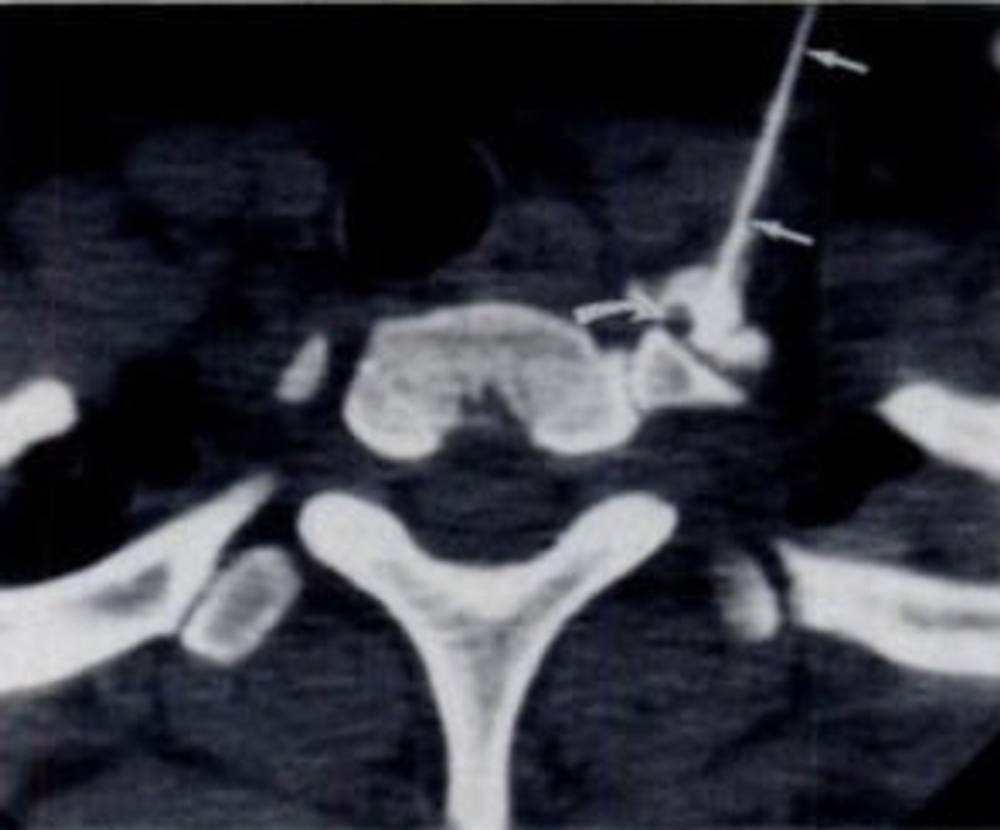

To assess a possible treatment for patients with long-term post-COVID parosmia, researchers looked at the potential benefits of CT-guided stellate ganglion block. Part of the autonomic nervous system, which regulates involuntary processes including heart rate, blood pressure, breathing and digestion, the stellate ganglia are nerves on each side of the neck. They deliver certain signals to the head, neck, arms and a portion of the upper chest.

The research team used a stellate ganglion block, which includes injecting anesthetic directly into the stellate ganglion on one side of the neck to stimulate the regional autonomic nervous system. The minimally invasive procedure takes less than 10 minutes, and no sedation or intravenous analgesia is necessary. Stellate ganglion block has been used with varying degrees of success to treat a number of conditions, including cluster headaches, phantom limb pain, Raynaud's and Meniere's syndromes, angina and cardiac arrhythmia.

CT guidance was used to position a spinal needle at the base of the neck for injection into the stellate ganglion. The researchers added a small dose of corticosteroid to the anesthetic in the pharmacologic preparation, suspecting that the COVID virus may be causing nerve inflammation.

Figure 1. CT-guided stellate ganglion injection. (Courtesy of Radiology)